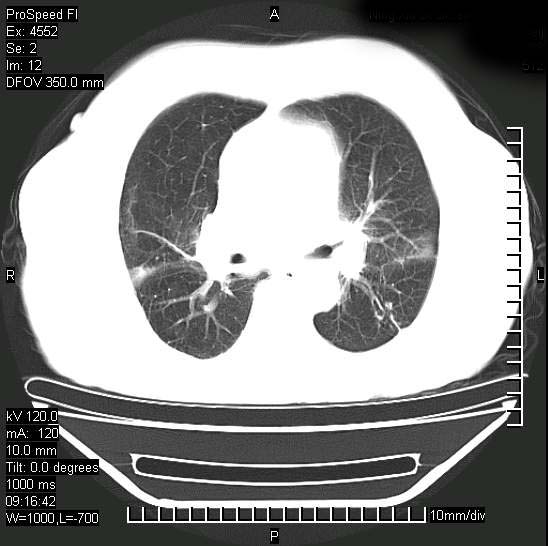

今天ct

短短几天内,病变范围明显增多扩大,以左侧明显,而且双侧出现胸水,还是考虑感染.

支持  结核ban感染,节段性肺不张,支气管内膜结核可能

继发性结核感染加重。左侧合并有支气管内膜结核。

1)两肺结核并感染。2)不排除左肺上叶中央型肺癌并阻塞性肺炎、肺不张可能;建议行纤支镜检查。3)右肺门及纵隔淋巴结肿大。4)双侧胸腔积液。

陈旧性肺结核及左下肺不张,咯血后肺部感染,双胸腔积液,高热可能与痰液引流不畅有关。